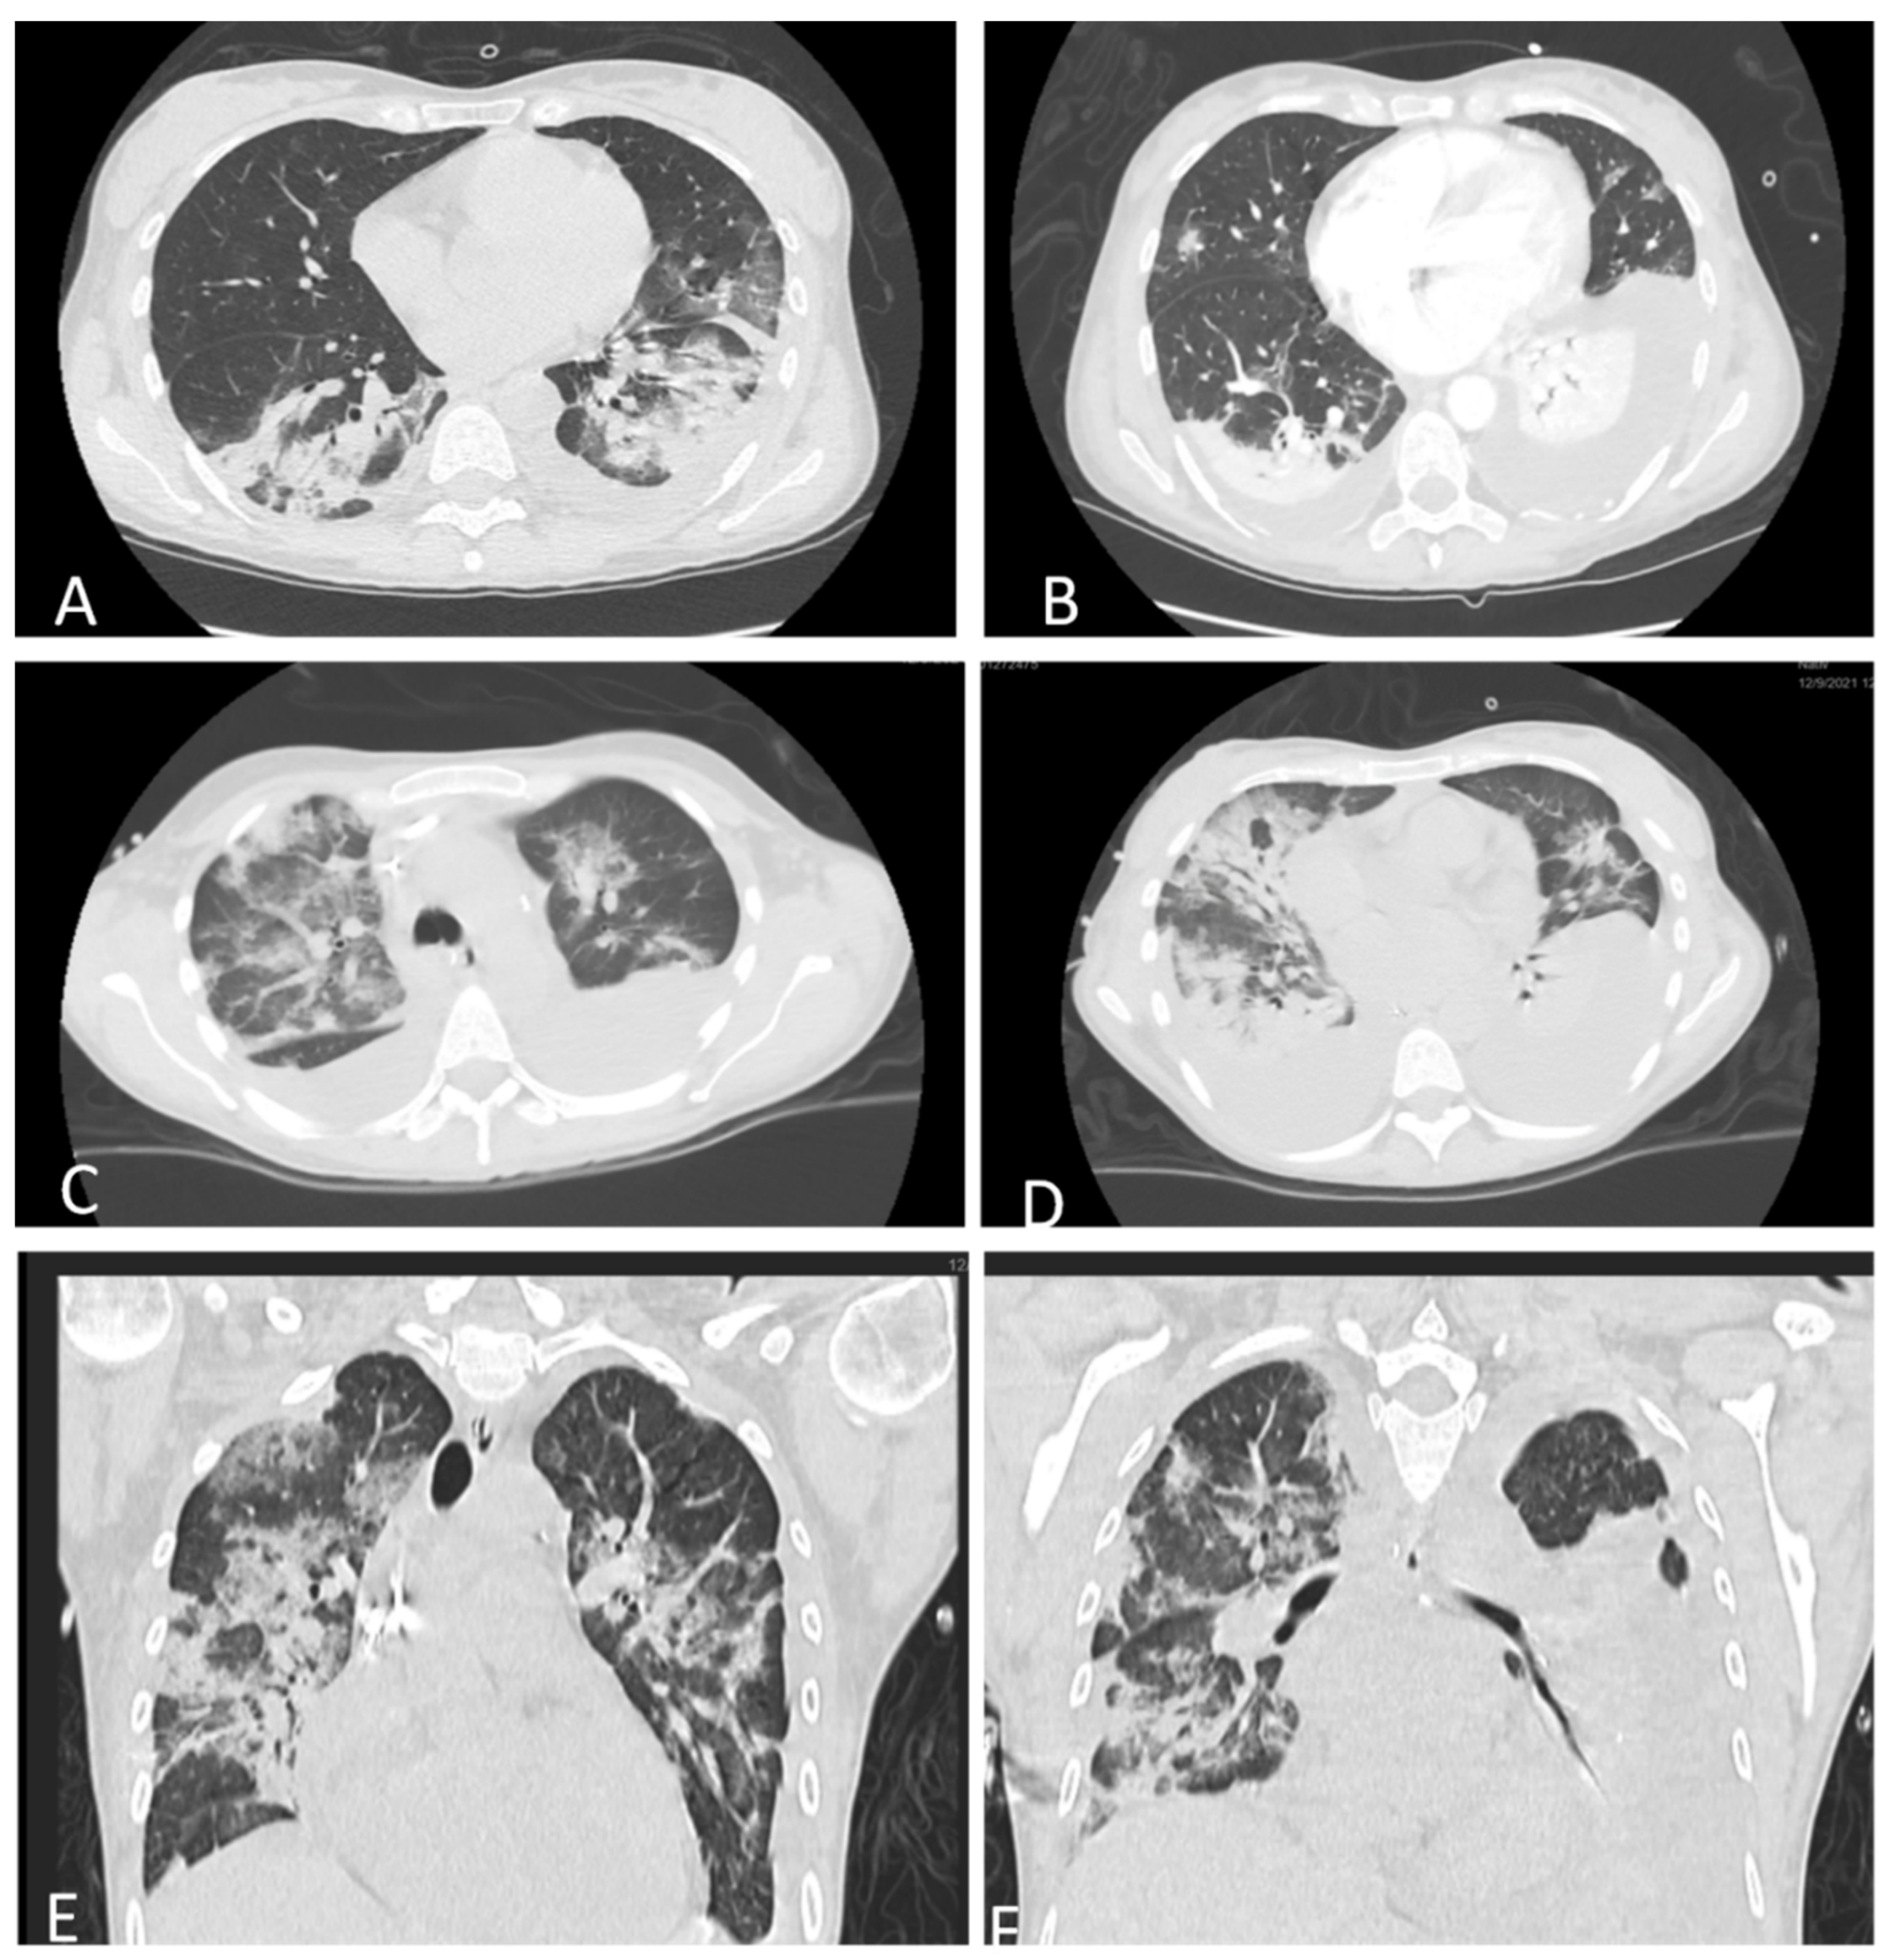

On admission, lab tests revealed mild anemia, lymphopenia, and inflammatory syndrome defined by increased levels of C-reactive protein (CRP), D-dimers, and lactate dehydrogenase (LDH). Renal and liver function tests were in the normal range. Extended biological parameters on admission and the trends are listed in Table 1. A thoracic native computer tomography (CT) scan revealed moderate pneumonia affecting 30% of the lungs (Figure 2A). The thoracic CT scan showed bilateral pleural effusions (Figure 2B). Based on these findings, together with the positive RT-PCR and respiratory failure, the diagnosis of a severe form of COVID-19 pneumonia was established. Following delivery, further investigations revealed elevated lipase levels of 2273 IU/L, which were three times higher than the normal value. Clinical and biological data were in favor of acute pancreatitis as indicated by the Atlanta definition [6]. The diagnosis was confirmed by a contrast-enhanced abdominal CT scan, which revealed a pancreas with increased volume and edema, with exudative changes causing liquid collections anterior and posterior to the pancreatic head and within the peritoneal cavity without signs of infection or abscesses (Figure 3A). The diagnosis of AP was established with the following severity scores: SAPS = 17 (2.6%), APACHE = 7 (7.6%), and SOFA = 1 (<10%).

A thoraco-abdominal CT scan repeated on day 10 revealed massive bilateral pleural effusion (Figure 2C–E) and progressing edematous pancreatitis. Due to a high suspicion of infection, cultures were obtained. The results of the cultures are listed in Table 2.

Figure 2. Thoracic CT scan. (A) Native thoracic scan showing bilateral COVID-19 pneumonia, affecting 30% of the lungs, and minimal right pleural effusion. (B) Contrast-enhanced thoracic CT scan revealing medium right pleural effusion and bilateral COVID-19 pneumonia. (C,D) Native thoracic CT scan, transversal view with bilateral pleural effusions and bacterial pneumonia. (E,F) Native thoracic CT scan, sagittal view with large right pleural effusion, inferior right lobe atelectasis, and bacterial pneumonia.